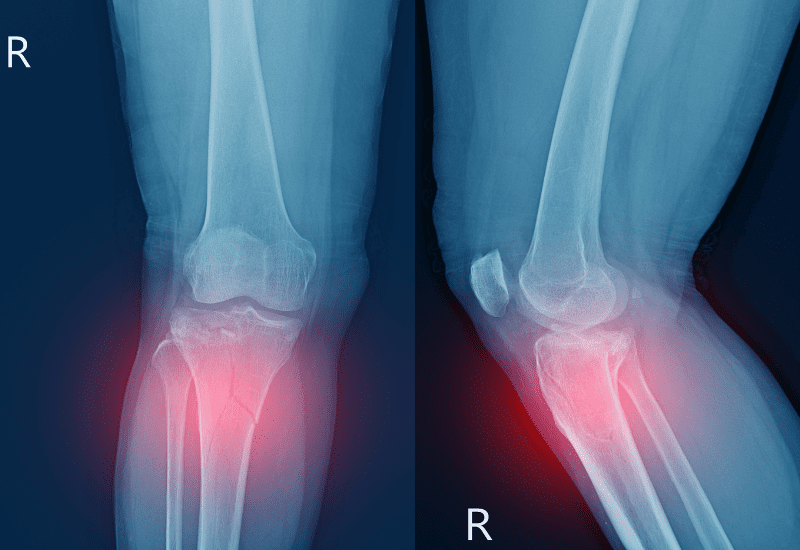

Fracturas de rótula

Una caída o impacto fuerte puede fracturar la rótula.

Dolor intenso, inflamación y dificultad para extender la pierna son señales de alerta.

Pruebas de imagen

- Rayos X: detectan fracturas.